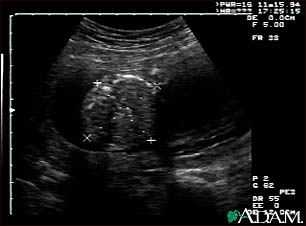

Ultrasound, normal fetus - abdomen measurements

This is a normal fetal ultrasound performed at 19 weeks gestation. Many health care providers like to have fetal measurements to verify the size of the fetus and to look for any abnormalities. This ultrasound is of an abdominal measurement. It shows a cross-section of the abdomen, and the measurements are indicated by the cross hairs and dotted lines.